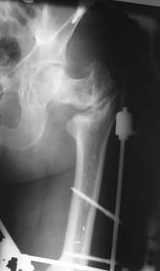

В приложении пример пациента, близкого по картине к тому, что представил Виктор (варус и смещение периферического отломка на поперечник кзади). Сделали как раз то, что Виктор исходно намеревался - аппаратная коррекция и затем гамма.